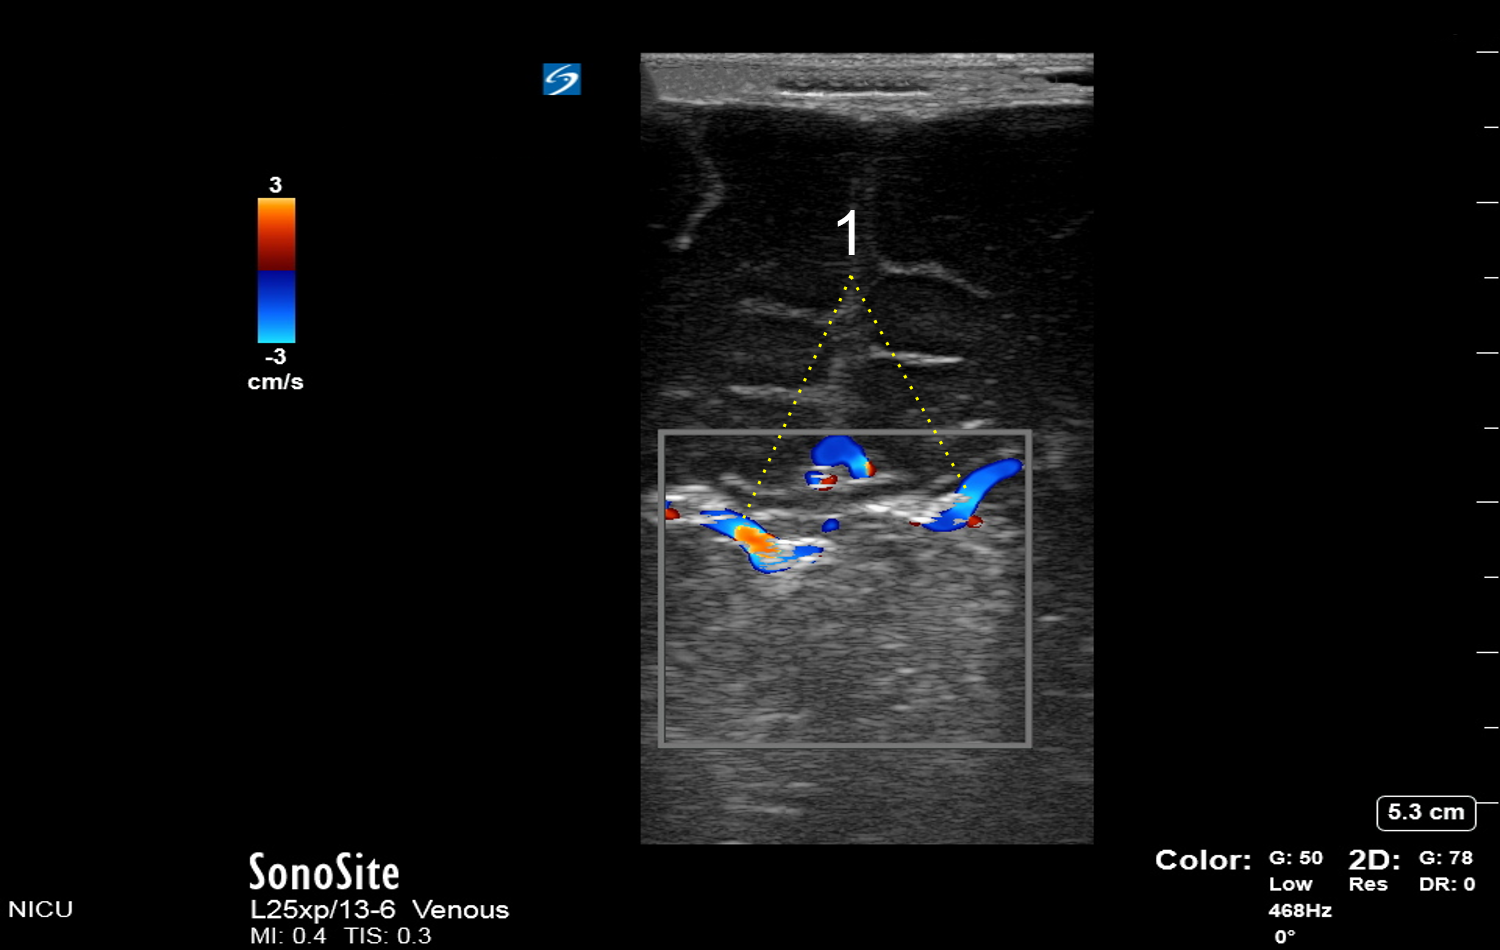

Neonatology Terminal Veins Image

Terminal Veins